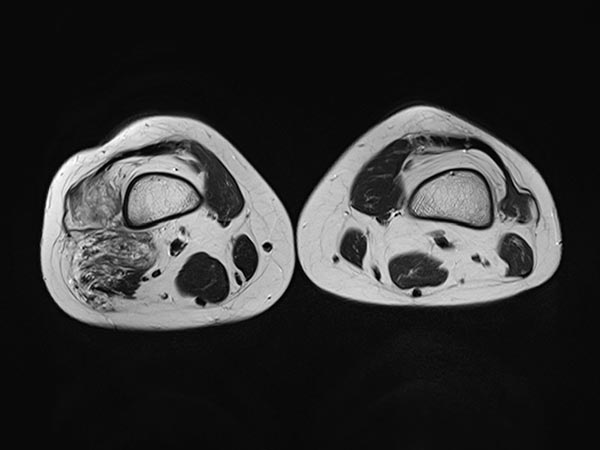

Axial T2-weighted MRI, fat-suppressed, shows the close relationship to the periosteum of the femur. This location is particularly painful due to inflammatory irritation of the periosteum.

T2-weighted MRI without fat suppression in the axial plane reveals inflammatory, fibrotic remodeling of the lesion due to multiple inflammations. The right vastus lateralis of the quadriceps femoris muscle is completely penetrated by the lesion.